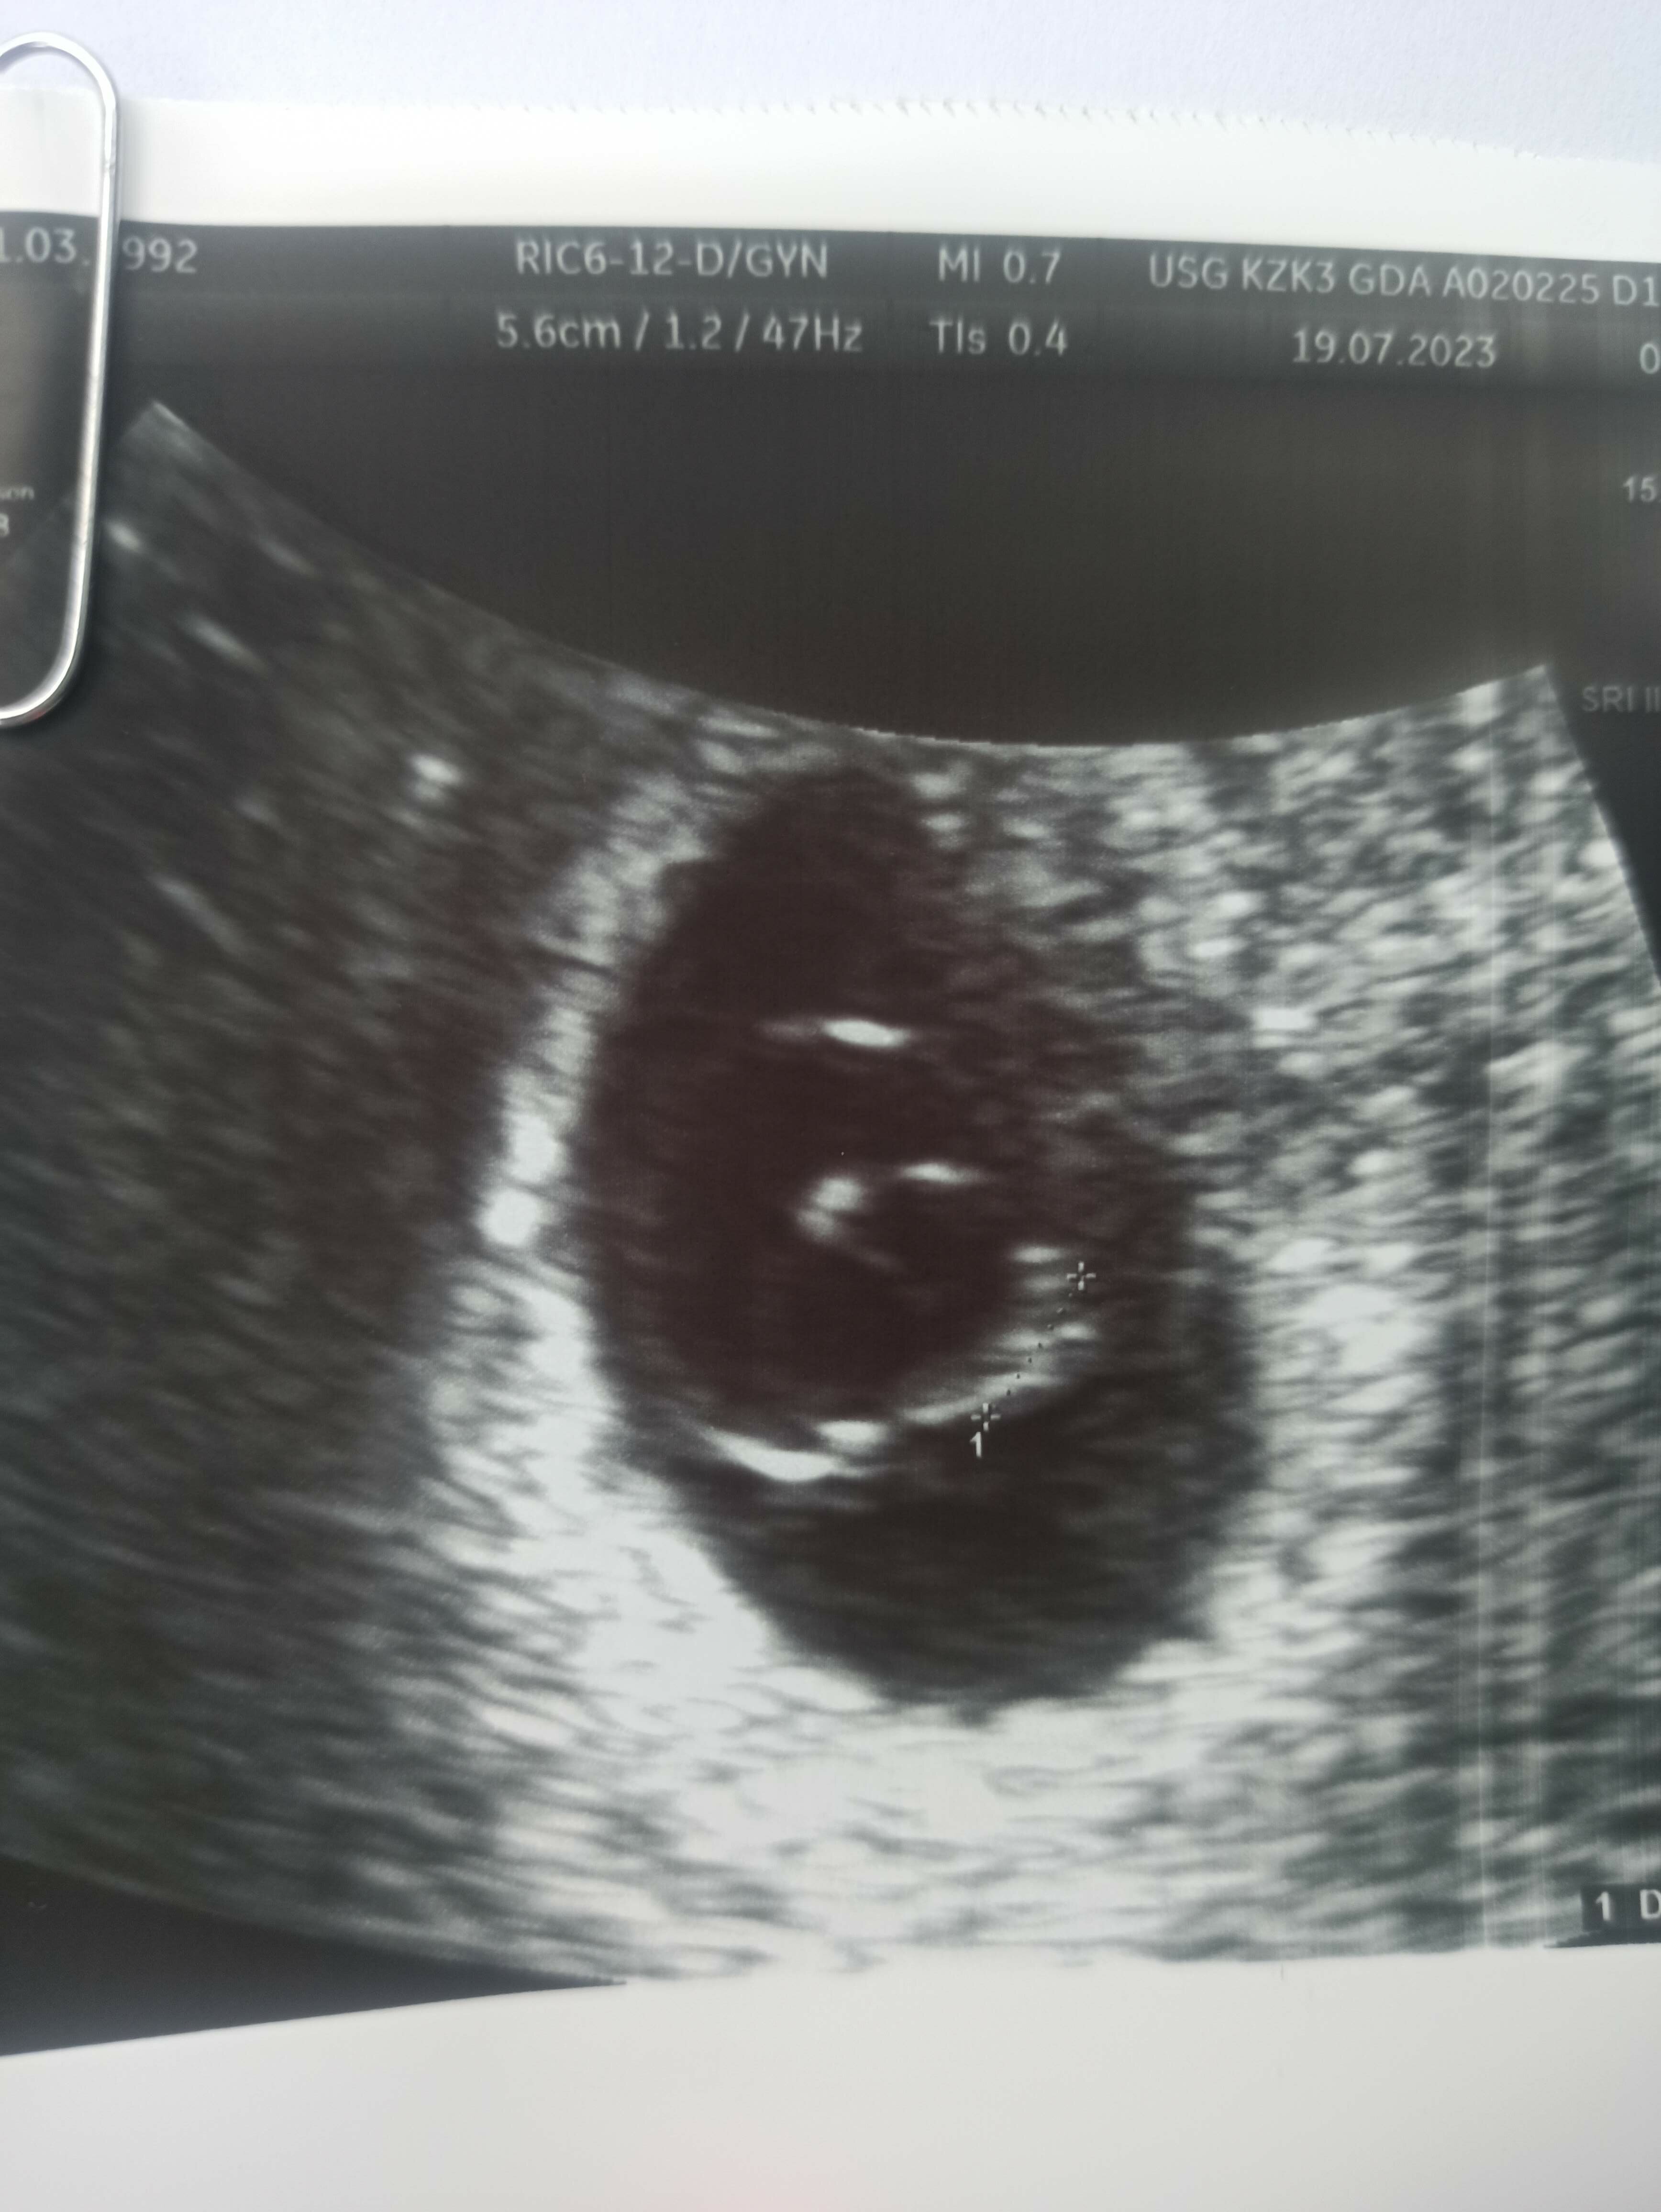

Dziś tylko przeżył jeden zarodek ma 4 mm i jest to ten młodszy i są przepływy, lekarz oceniła to jako puls +/-. Powiedziała że różnie może być, tak bywa z ciążami bliźniaczymi i muszę zrobić badanie krwi do jasnej informacji

Ma ktoś takie doświadczenie? Zdjęcie z dziś